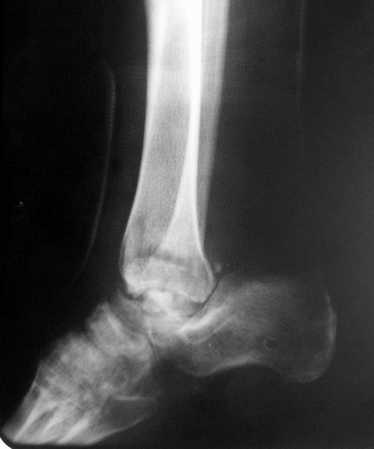

Последствия открытого переломо - вывиха таранной кости

Просим совета в лечении пациента с последствиями тяжелой сочетанной травмы. Пациент С., 41 года, по профессии бизнесмен, в сентябре 2005 г. пострадал в дорожно-транспортном происшествии (упал с мотоцикла). Диагноз: ЗЧМТ, ушиб головного мозга тяжелой степени. Открытый переломо-вывих левой таранной кости. Закрытые переломы лонной и седалищной костей слева.

Был доставлен в НИИСП им. Н.В. Склифосовского. При ПХО раны выявлен открытый перелом левой таранной кости (III тип по Hawkins) с утратой вывихнутого тела таранной кости. Выполнена ПХО, фиксация голени и стопы стержневым аппаратом. Рана зажила без осложнений. Аппарат демонтирован через 1,5 месяца. В настоящее время больной предъявляет жалобы на боль в голеностопном суставе при нагрузке. Передвигается с опорой на костыли с дозированной нагрузкой на левую стопу. Голень и стопа фиксированы циркулярной пластиковой повязкой. Сохраняются остаточные явления ЧМТ (в виде сниженной критики к своему состоянию и определенной недисциплинированности в выполнении врачебных рекомендаций) Рентгенограммы – рис. 1, 2 (просим извинения за низкое качество рентгенограмм), схема – рис. 3.